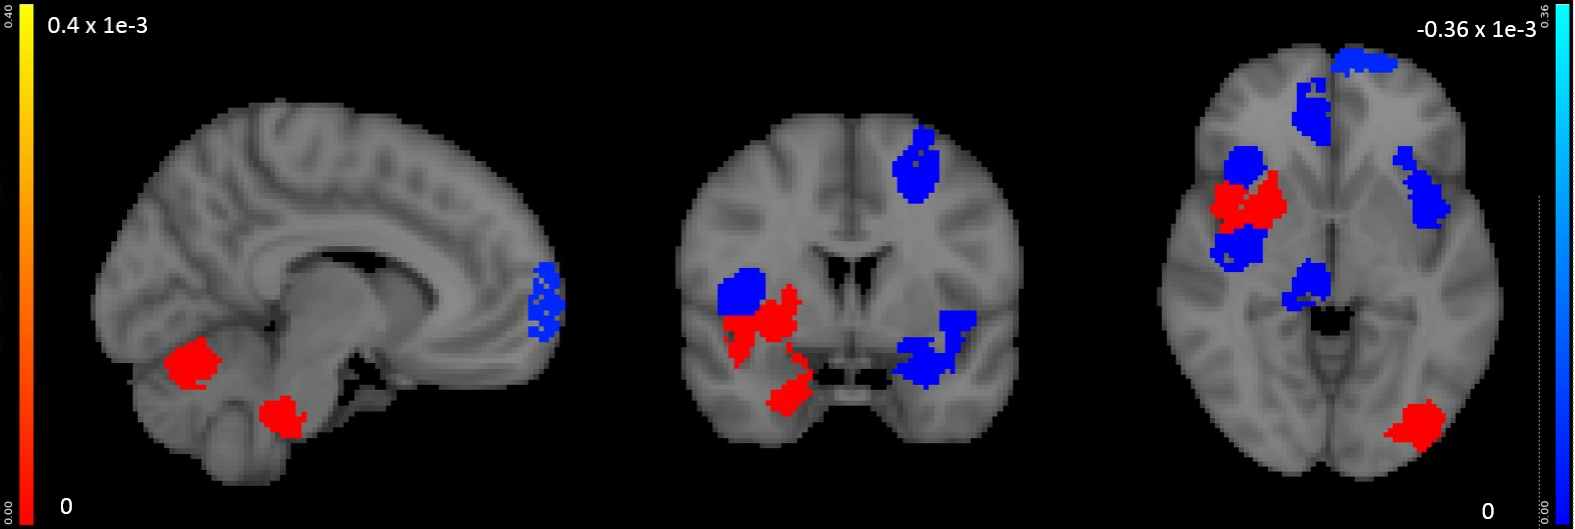

(b) Voxel-level random forest model for change of SRS after treatment

To predict treatment outcome from baseline fMRI scan, Dvornek et al. achieved correlation r=0.83 between predictions and measurements [20]. We achieved r=0.71 (Fig. 6(b)). However, the study by Dvornek et al. takes pre-selected regions as input and loses interpretability because it does not perform region selection. In contrast, our proposed approach takes a whole-brain image as input and can select predictive regions for interpretation and biomarker selection. Furthermore, the proposed approach is generic and any non-linear model (including Dvornek’s method) can be applied.

(a) Region-level elastic net model for pre-treatment SRS

Neurosynth decoder results (Fig. 9(d), Fig. 10 right figure) show that selected regions match the literature [11]. The selected regions are slightly different across experiments due to different tasks, datasets and target measures. Many regions are shared across experiments, such as prefrontal cortex and visual cortex.